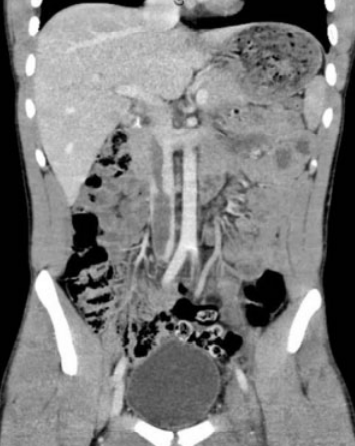

- Risque plus rare de Thromboses comme complication → HITT

- Thromboses artérielles ou veineuses

- Suspicion+++ si présence de Thromboses Artéreilles ET veineuses simulatnées